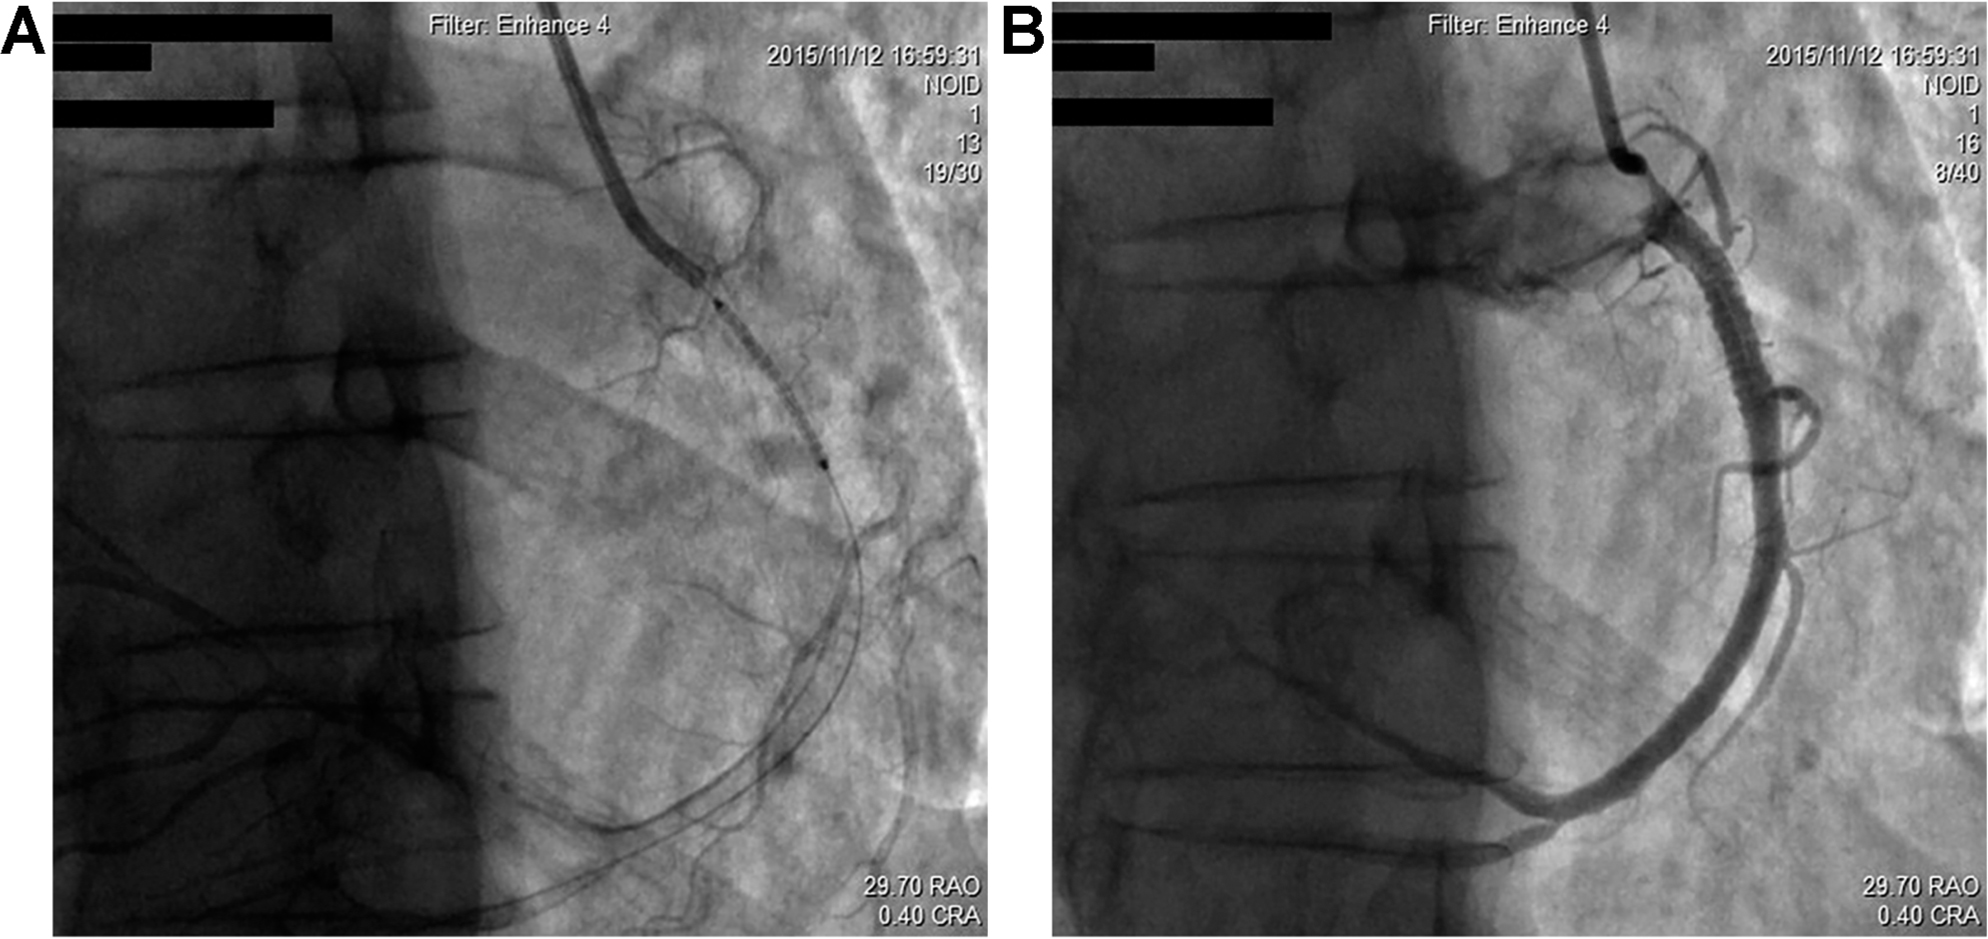

Regarding angiographic findings, no hemodynamically significant stenosis of left anterior descending artery (LAD), left main coronary artery (LM), left circumflex artery (LCX), and antegrade TIMI III flow was found ( Fig. 2). The RCA, as a dominant vessel, was thick with 80% diameter stenosis ( Fig. 3). Assuming this site to be the cause of discomfort, we proceeded with surgical intervention to open the occluded RCA. After balloon pre-dilatation, a Xience V® 3.0 × 23 mm (Abbott Vascular, Santa Clara, CA, USA) drug-eluting stent was subsequently implanted at the lesion site (Fig.4A), using an inflation pressure of 16 atm for 20s. The intervention was successful, achieving optimal antegrade TIMI III flow without residual stenosis (Fig. 4B). The patient’s recovery post-angioplasty was uneventful.

A drug-eluting stent was subsequently implanted at the lesion site and the intervention achieved optimal antegrade TIMI III flow without residual stenosis.